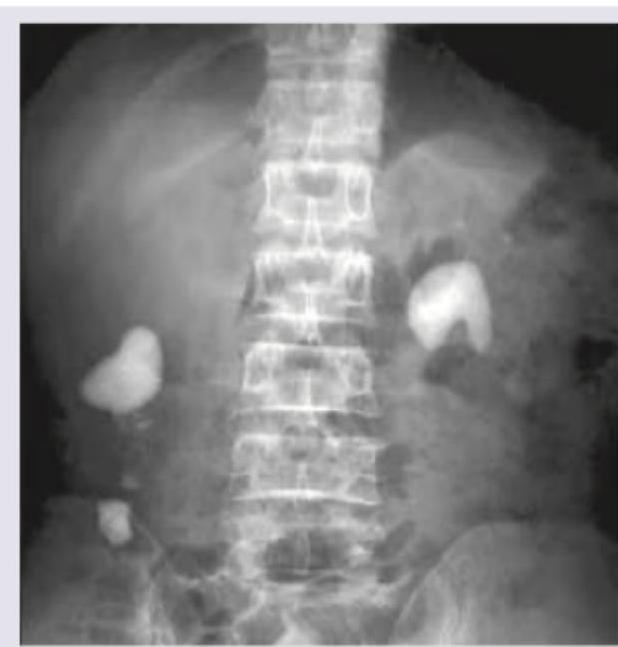

Question 25: Which of the following kidney stones best explains the findings in this X-ray KUB?

- A. Xanthine

- B. Phosphate

- C. Uric acid (Correct Answer)

- D. Cystine

Explanation: ***Uric acid*** - The X-ray KUB image shows **radio-lucent stones** (stones that are not visible) within the kidneys, which is characteristic of **uric acid** stones. - Uric acid stones appear radio-lucent because they **do not contain calcium** and have a low atomic number, making them poorly visible on plain radiographs. *Xanthine* - **Xanthine stones** are also typically **radio-lucent** on X-ray, similar to uric acid stones. - However, they are much **rarer** than uric acid stones, often associated with genetic disorders of purine metabolism or allopurinol use. *Phosphate* - **Phosphate stones**, such as **calcium phosphate** and **magnesium ammonium phosphate (struvite)** stones, are typically **radio-opaque** and appear bright white on X-ray. - Struvite stones often grow large, forming **staghorn calculi**, which is not depicted as a radio-opaque lesion here. *Cystine* - **Cystine stones** are usually **faintly radio-opaque** or **semi-opaque** on X-ray, appearing less dense than calcium stones but more dense than uric acid stones. - They tend to form in acidic urine environments due to a genetic defect in amino acid transport.